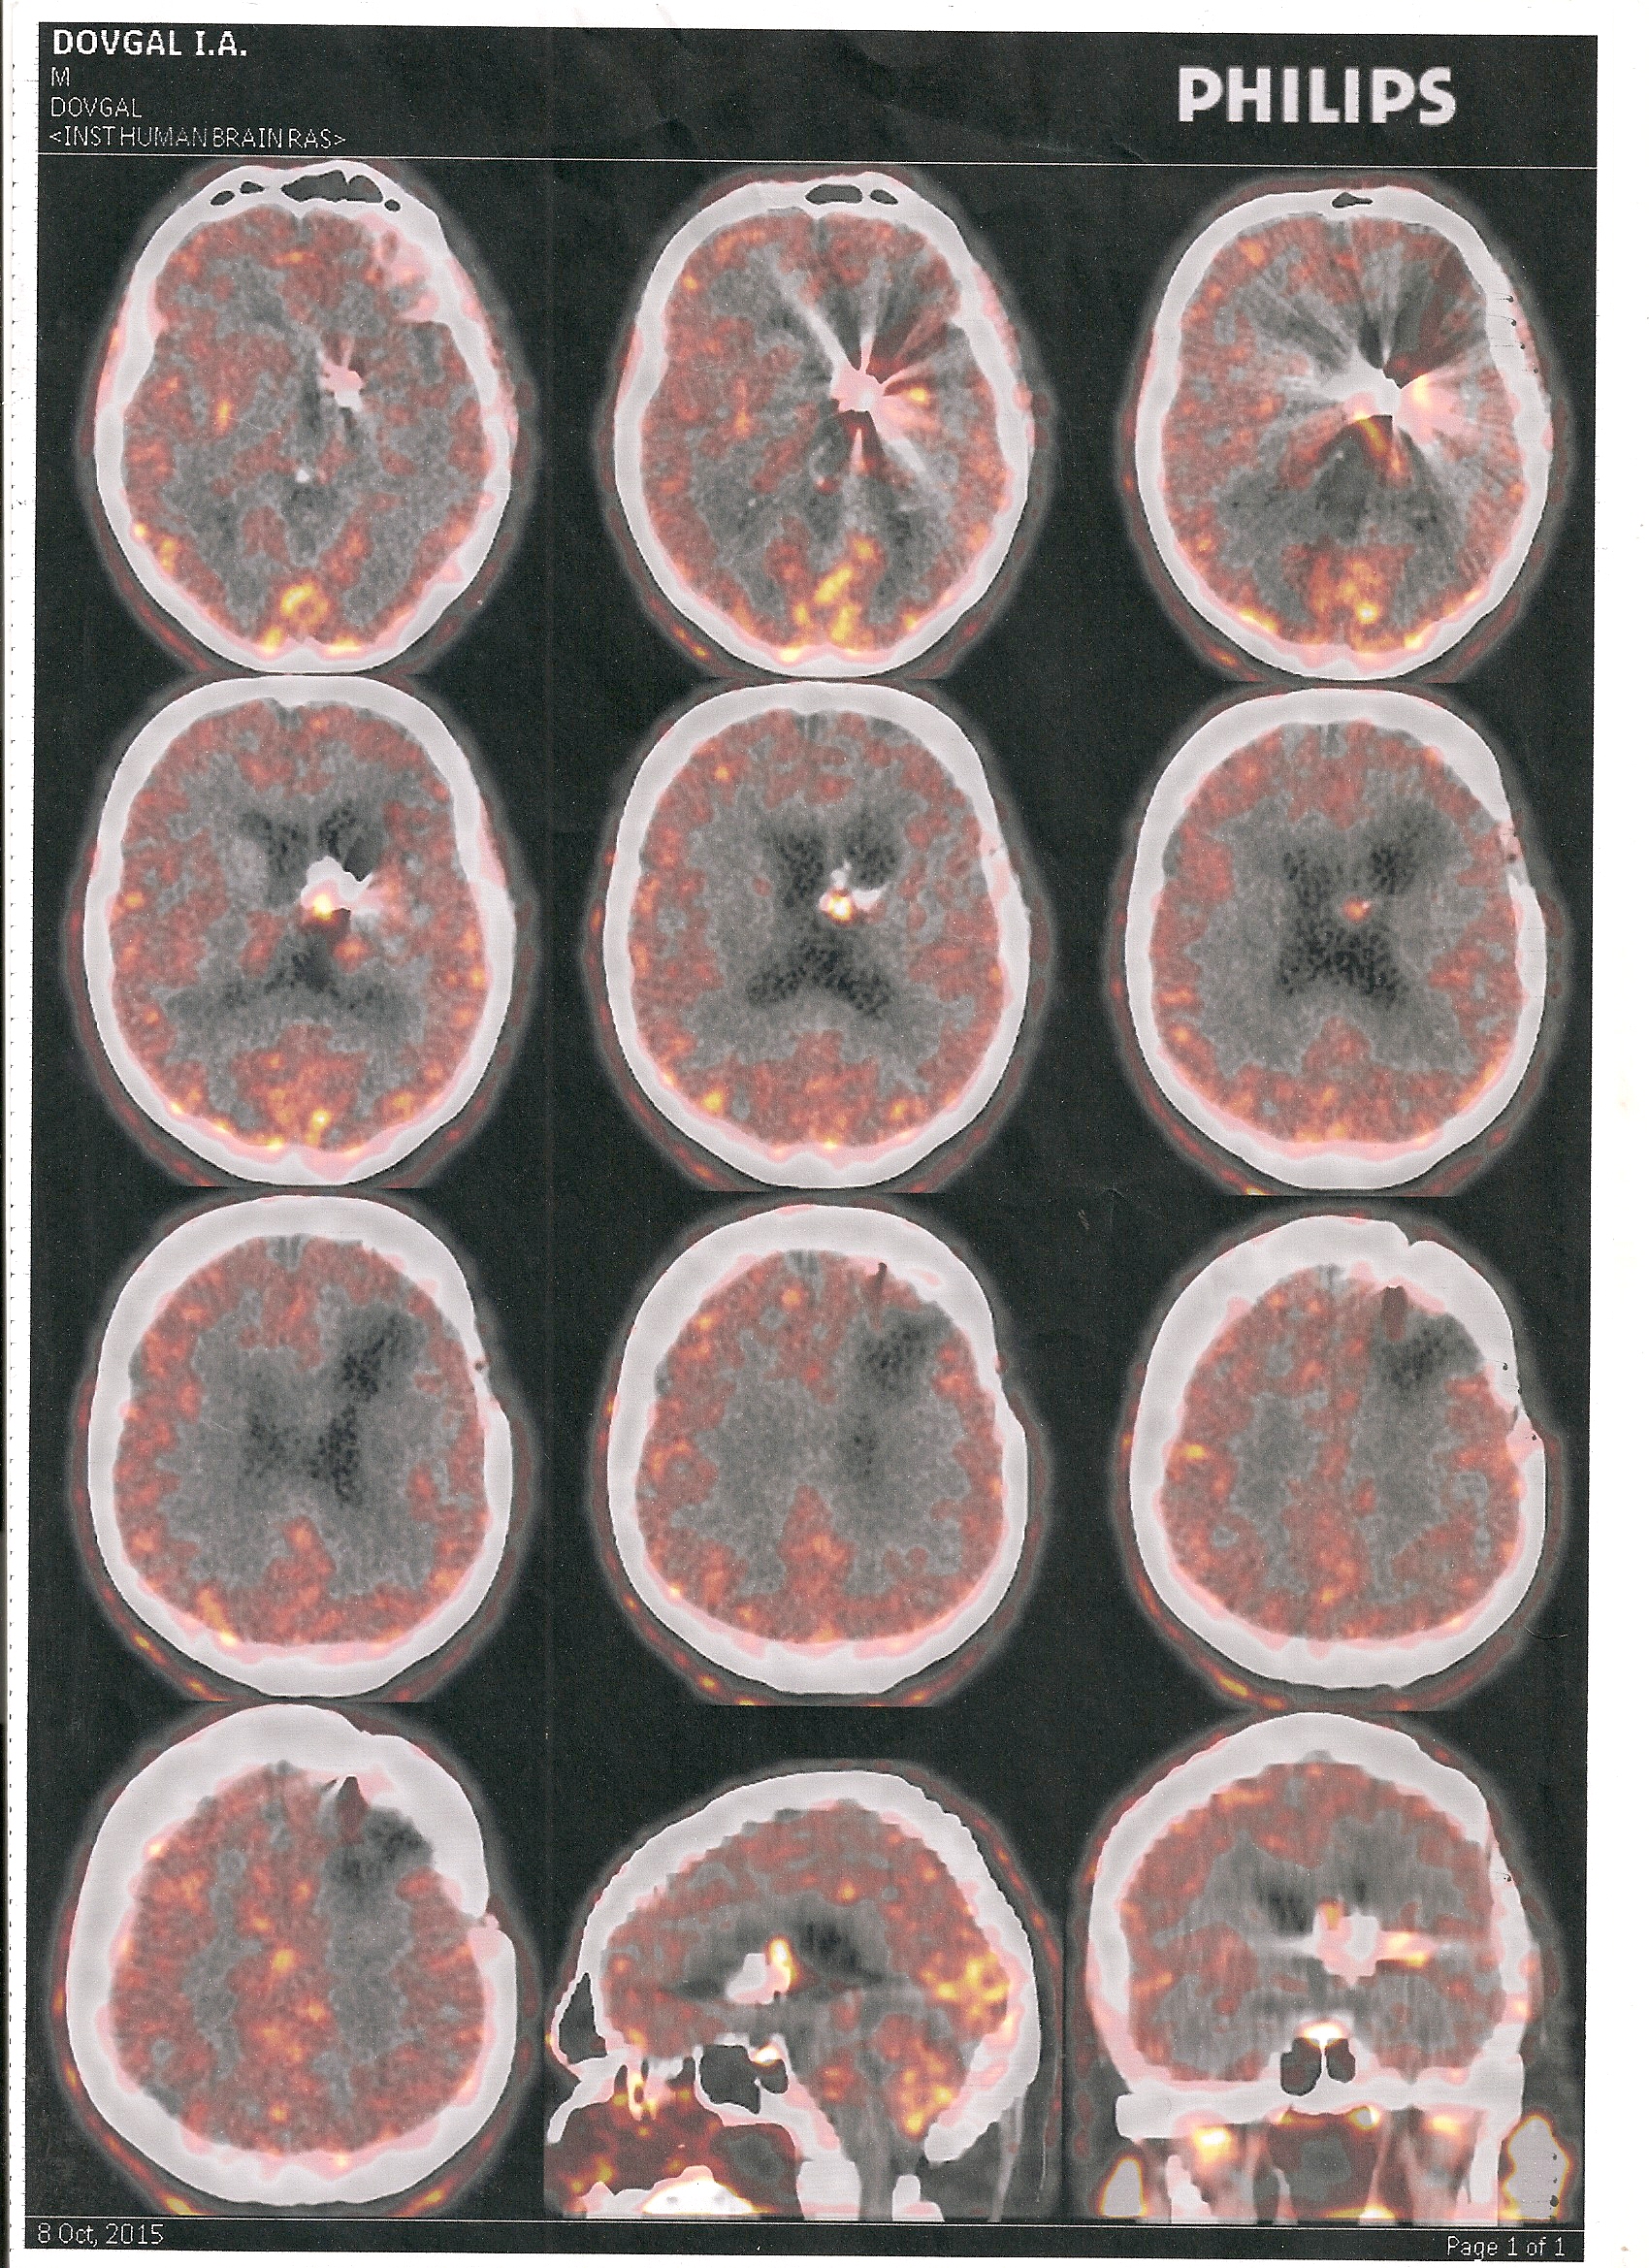

Сделал ПЭТ-КТ на фоне ухудшения самочувствия: периодическое непроизвольное бросание в жар, также периодические в районе операции тянущие головные боли, пока терпимые, изменение зрения левого глаза(вблизи стал видеть хуже), и по-моему глаза покраснели.

При исследовании с метионином в средней трети левой лобной доли определяется аметаболический очаг размерами 25*25**24 мм, обусловленный послеоперационной кистой. В стенках описанной кисты очагов патологически повышенного накопления РФП не выявлено.

В левом боковом желудочке определяется очаг патологически повышенного накопления РФП(ИН=1,33) 14*12*11 мм. При КТ-исследовании в описанном участке регистрируются массивные отложения извести.

В остальных структурах ГМ очагов патологической фиксации РФП не обнаружено.

При КТ-исследовании патологически кровоизлияний не выявлено.

Состояние после лечения олигодендроглиомы левой лобной доли с низкой метаболической активностью остатка глиомы.

ПЭТ-данных за продолженный рост опухоли не получено.

Высылаю снимки ПЭТ-КТ.

сканирование0001.jpg

ПЭТ-КТ Довгаль И. А.